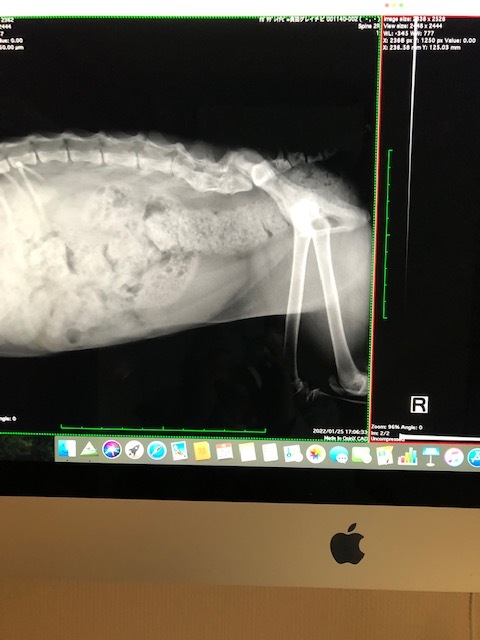

CT,MRIにむけてレントゲンを撮りました。

567がくっついている。やはりCT,MRIの必要が・・・というお話でした。